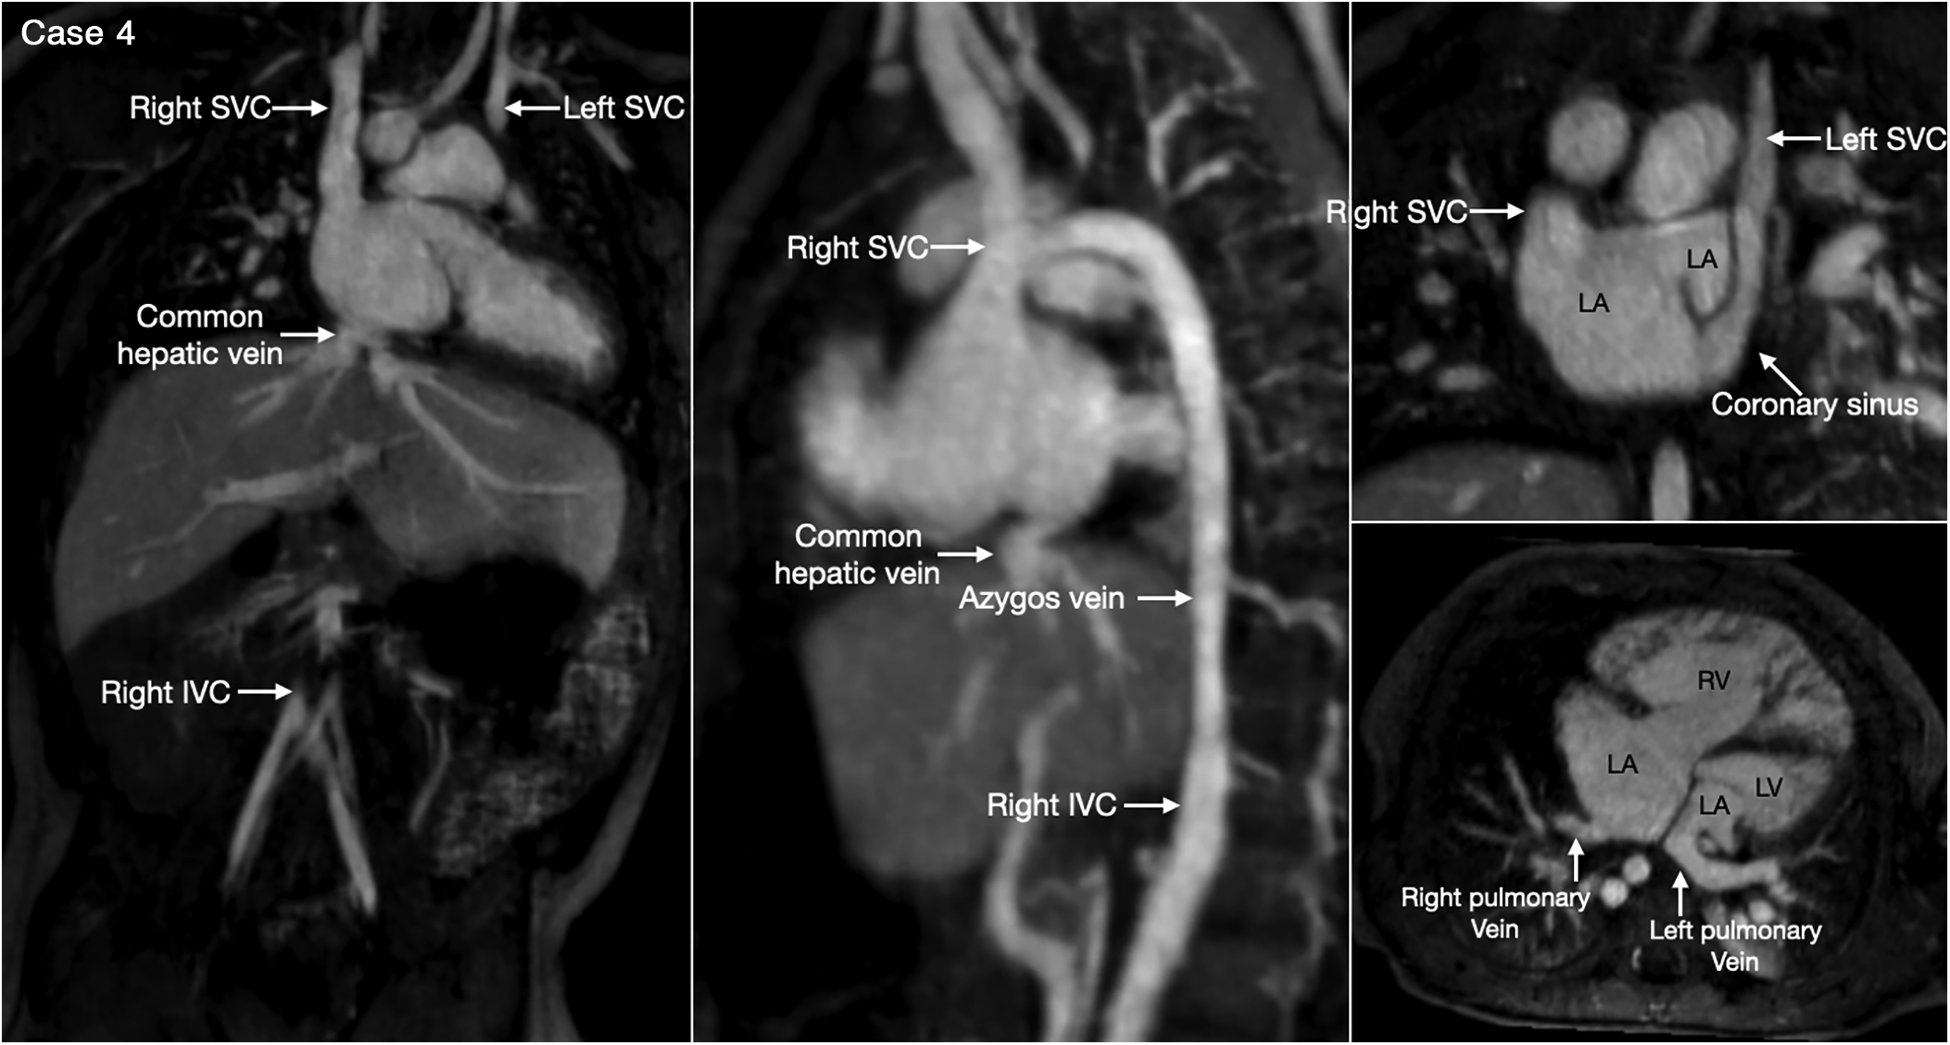

Figure 5

(Case 4). Bilateral superior venae cavae and interrupted inferior vena cava in a patient with heterotaxy and left isomerism. There is no bridging vein between the two superior venae cavae (SVC). The left SVC connects to the coronary sinus that drains to the right-sided left atrium (LA). The right-sided inferior vena cava (IVC) is interrupted and continues to the right-sided SVC. The right and left pulmonary veins connect to the posterior wall of the ipsilateral left atrium. There is a large defect involving the most superior part of the atrial septum. There is myocardial noncompaction of the left ventricle (LV). RA, right atrium; RV, right ventricle.